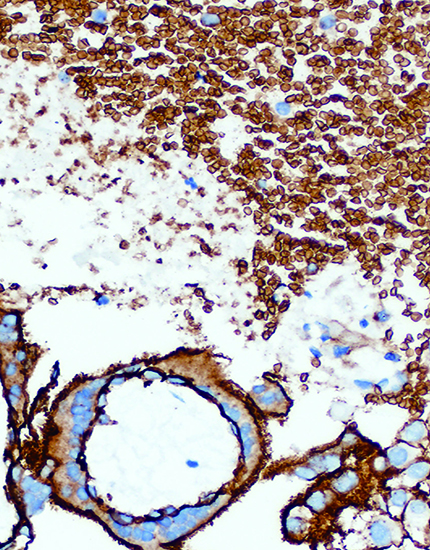

产品名称:Granzyme B (GrB)

产品编号:RMA-0814

阳性部位:胞质

图片描述:

NK/T细胞淋巴瘤,Granzyme B染色,胞质阳性